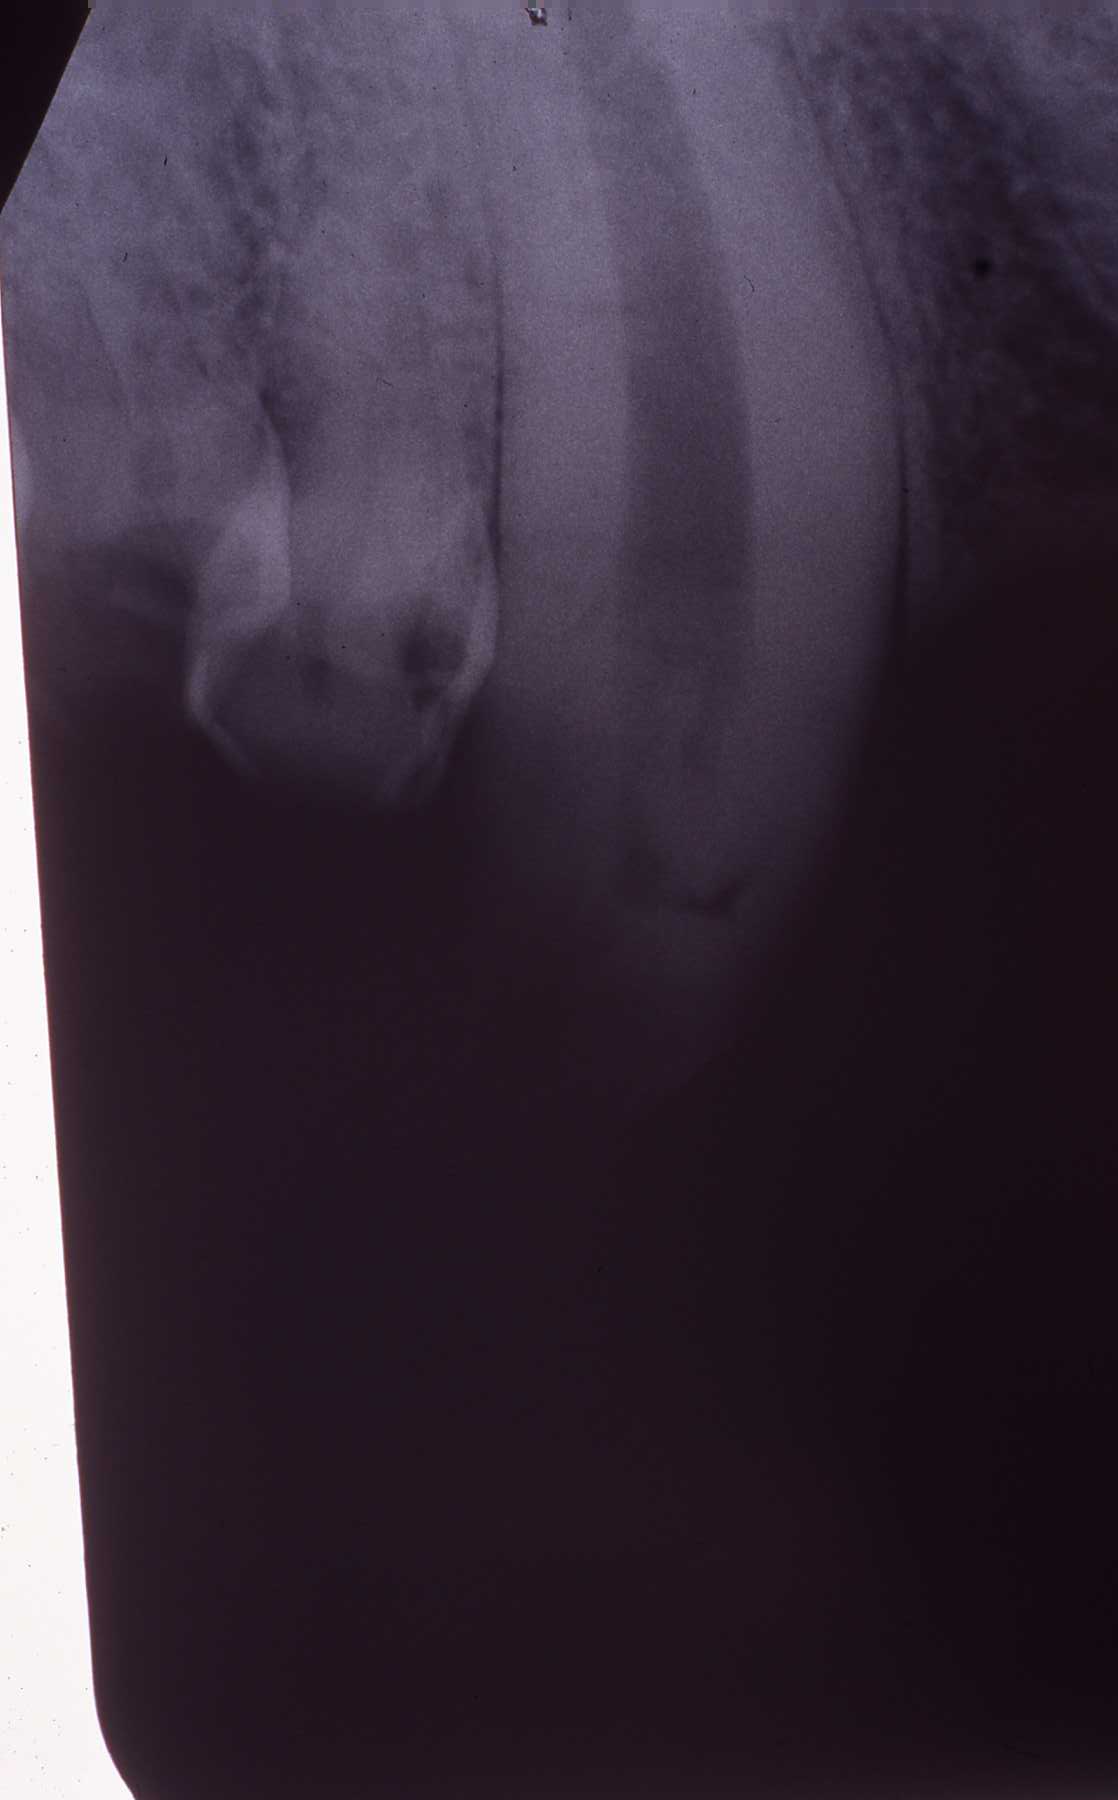

Preoperative radiograph. Note large diameter canine root canal in this young animal

Working length radiograph, 40 mm

Endo fill radiograph